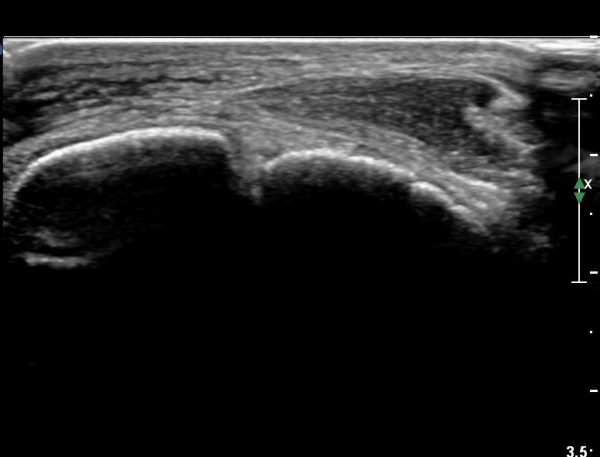

¹ß¸ñ ¾ÕÂÊ Á¾´Ü¸é°Ë»ç¿¡¼­ °üÀý³» ºÎÁ¾À» º¸ÀδÙ(»çÁø 1).

°üÀý³» ºÎÁ¾Àº ½É°¢ÇÑ ¼Õ»óÀ» ¾Ï½ÃÇÏ´Â ¼Ò°ßÀÌ´Ù.

Àü°ÅºñÀδë Á¾´Ü¸é°Ë»ç¿¡¼­ Àü°ÅºñÀδëÀÇ ÆÄ¿­ÀÌ °üÂûµÈ´Ù(»çÁø 4, 5).